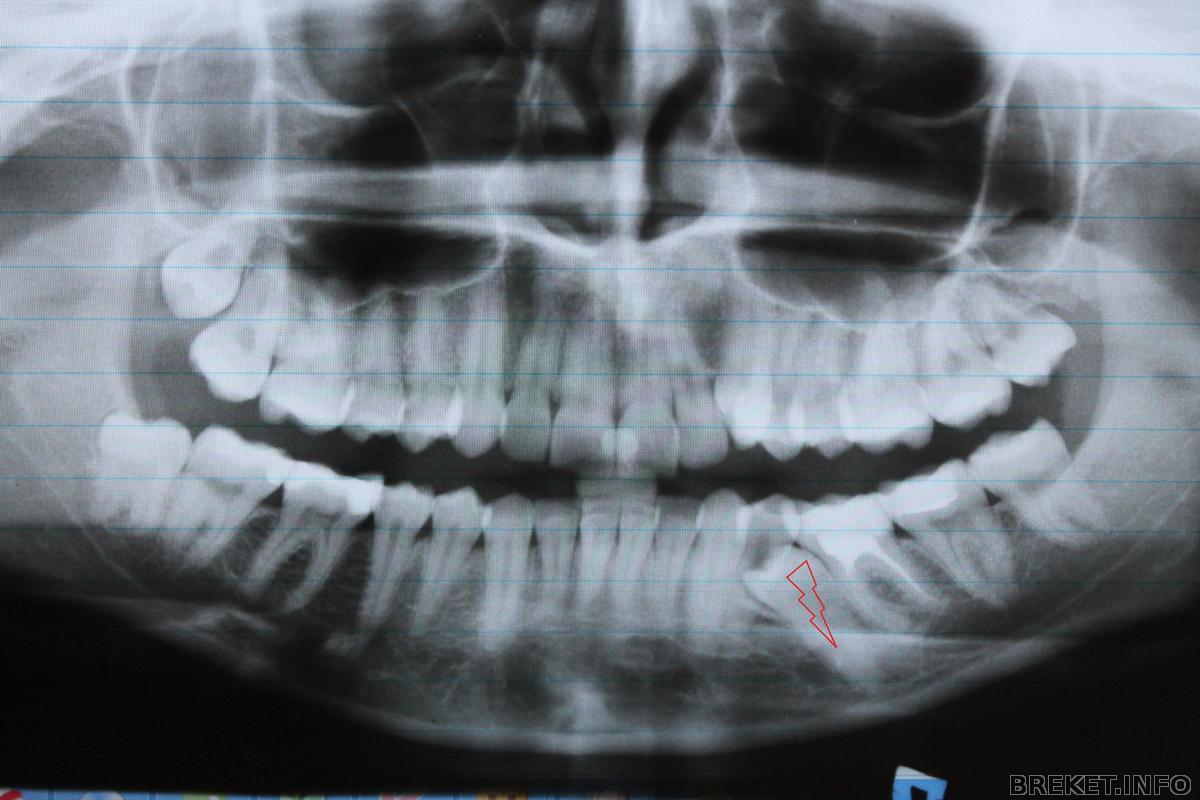

Меня волновал мой клык, он ужасен! Думала, что у меня не сложный случай и все будет хорошо и быстро. Но на снимке ретенированная пятерка.

1) Так как у меня тот вариант, когда зубы смыкаются хорошо и можно лечить только верх можно ничего не делать с НЧ и подключить её к лечению если появится необходимость (Я склоняюсь к этому варианту)

2) удалить 4 зуб и вытянуть пятерку, и лечить нижний ряд.

3) удалить 6 зуб и вытянуть пятерку ...